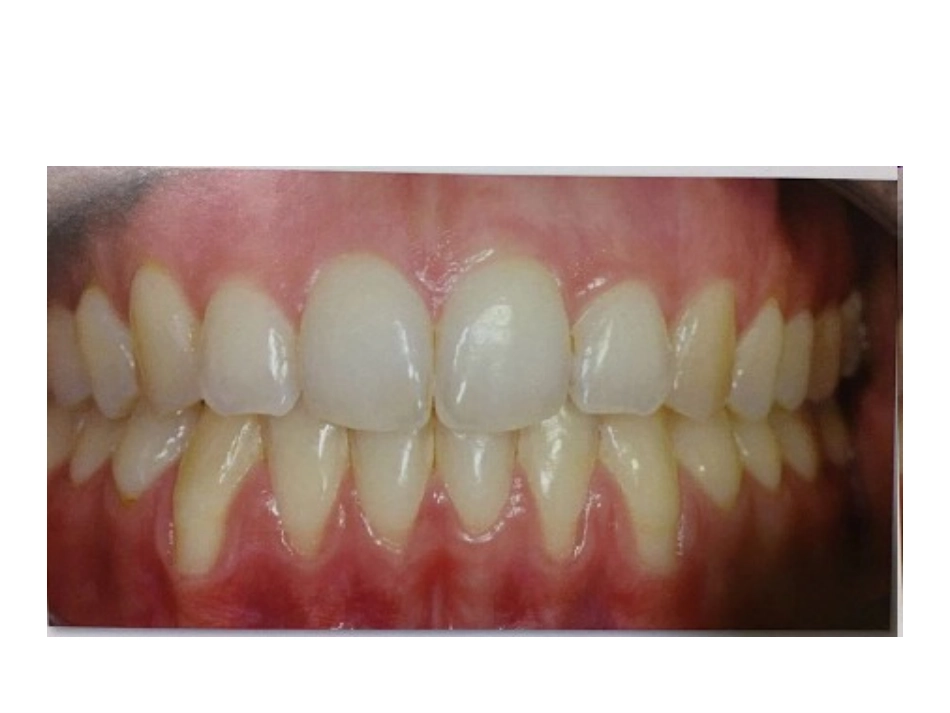

膜龈手术病例讨论•病例:女,28岁,银行职员。•主诉:自觉牙齿过长•现病史:患者自觉近年来牙齿逐渐变长,否认有刷牙出血病史以及系统性疾病史,现来我科要求治疗•口腔检查:全口恒牙列,口腔卫生状况尚可,牙龈无红肿,牙面、牙间未见明显软垢及结石,PD:2-3mm,BI:0-1,33,32,42,43可见明显牙龈退缩,GR:3mm,余牙未见明显异常。•请问1.诊断是什么?•2.如何治疗?牙周组织膜龈手术•膜龈手术(mucogingivalsurgery)是多种牙周软组织手术的总称,它们涉及附着龈、牙槽粘膜、系带或前庭沟区。•膜龈美学手术用于治疗膜龈美学异常。这种异常可由牙龈退缩造成,常伴有牙体非龋性颈部缺损和/或根面龋或被动萌出异常。膜龈手术的目的也包括增加修复体或种植体周围牙龈的厚度和高度以及增加无牙区牙槽嵴的软组织。牙龈退缩龋及非龋性颈部楔缺牙龈厚度/高度不足被动萌出异常牙周表型(periodontalphenotype)•1989年,Seibert&Lindhe根据牙龈的厚度、角化龈的宽度以及临床牙冠的宽、长之比将牙龈生物型分为两种基本类型,即厚平型牙龈(flat-thickgingiva)和薄扇形牙龈(scalloped-thingingiva)。•厚平型牙龈对应的牙齿形态为方圆形、颈部凸起明显、接触区相对大,而且靠近根方。厚平型牙龈的附着龈相对量大,骨结构较厚并能够抵抗急性创伤和炎症,但容易形成牙周袋和骨下袋。•薄扇形牙龈对应的牙齿形态为锥形牙齿、不明显的颈部凸起、邻面接触区小且靠近牙齿切端。薄扇形牙龈的附着龈相对量少,骨结构较薄易出现骨开裂或骨开窗,炎症时常发生快速骨丧失随着软组织退缩。附加松弛切口的冠向复位瓣•附加松弛切口的冠向复位瓣是治疗单牙牙龈退缩可供选择的技术之一。本方法技术简便,因其术区范围小,且无须从腭部取游离组织移植,患者容易接受。从美学角度而言,术后疗效也较好。•能否行冠向复位瓣的一个必要条件是:暴露牙根根方角化牙龈须有足够的厚度和高度(较浅的退缩至少1mm,≥5mm的退缩至少2mm)游离龈移植术•游离龈移植术指从供区获得覆盖角化上皮的结缔组织,将其移植到口腔中另一个部位。游离龈移植物通常从腭部粘膜获取,是含上皮层的结缔组织。由于覆盖于无血供牙根表面的移植组织的存活完全依赖于其与周围骨膜床之间的血管连接,该方法用于根面覆盖的效果(尤其是获得完全根面覆盖)不可预期。